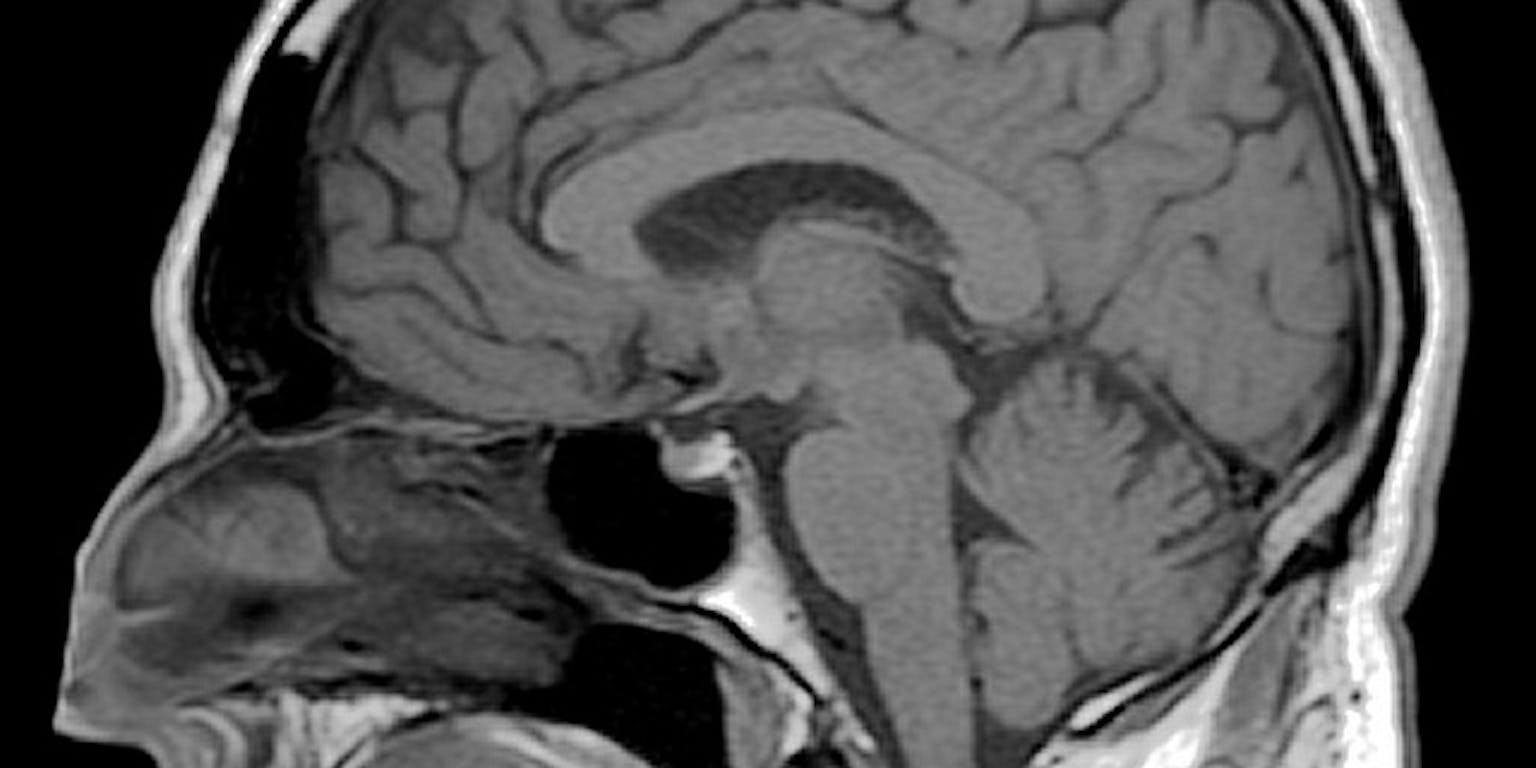

We krijgen altijd veel vragen van mensen die mee gaan doen aan een van onze onderzoeken. Doet zo’n MRI-scan pijn? Duurt het onderzoek lang? Waarom zou je eigenlijk meedoen?